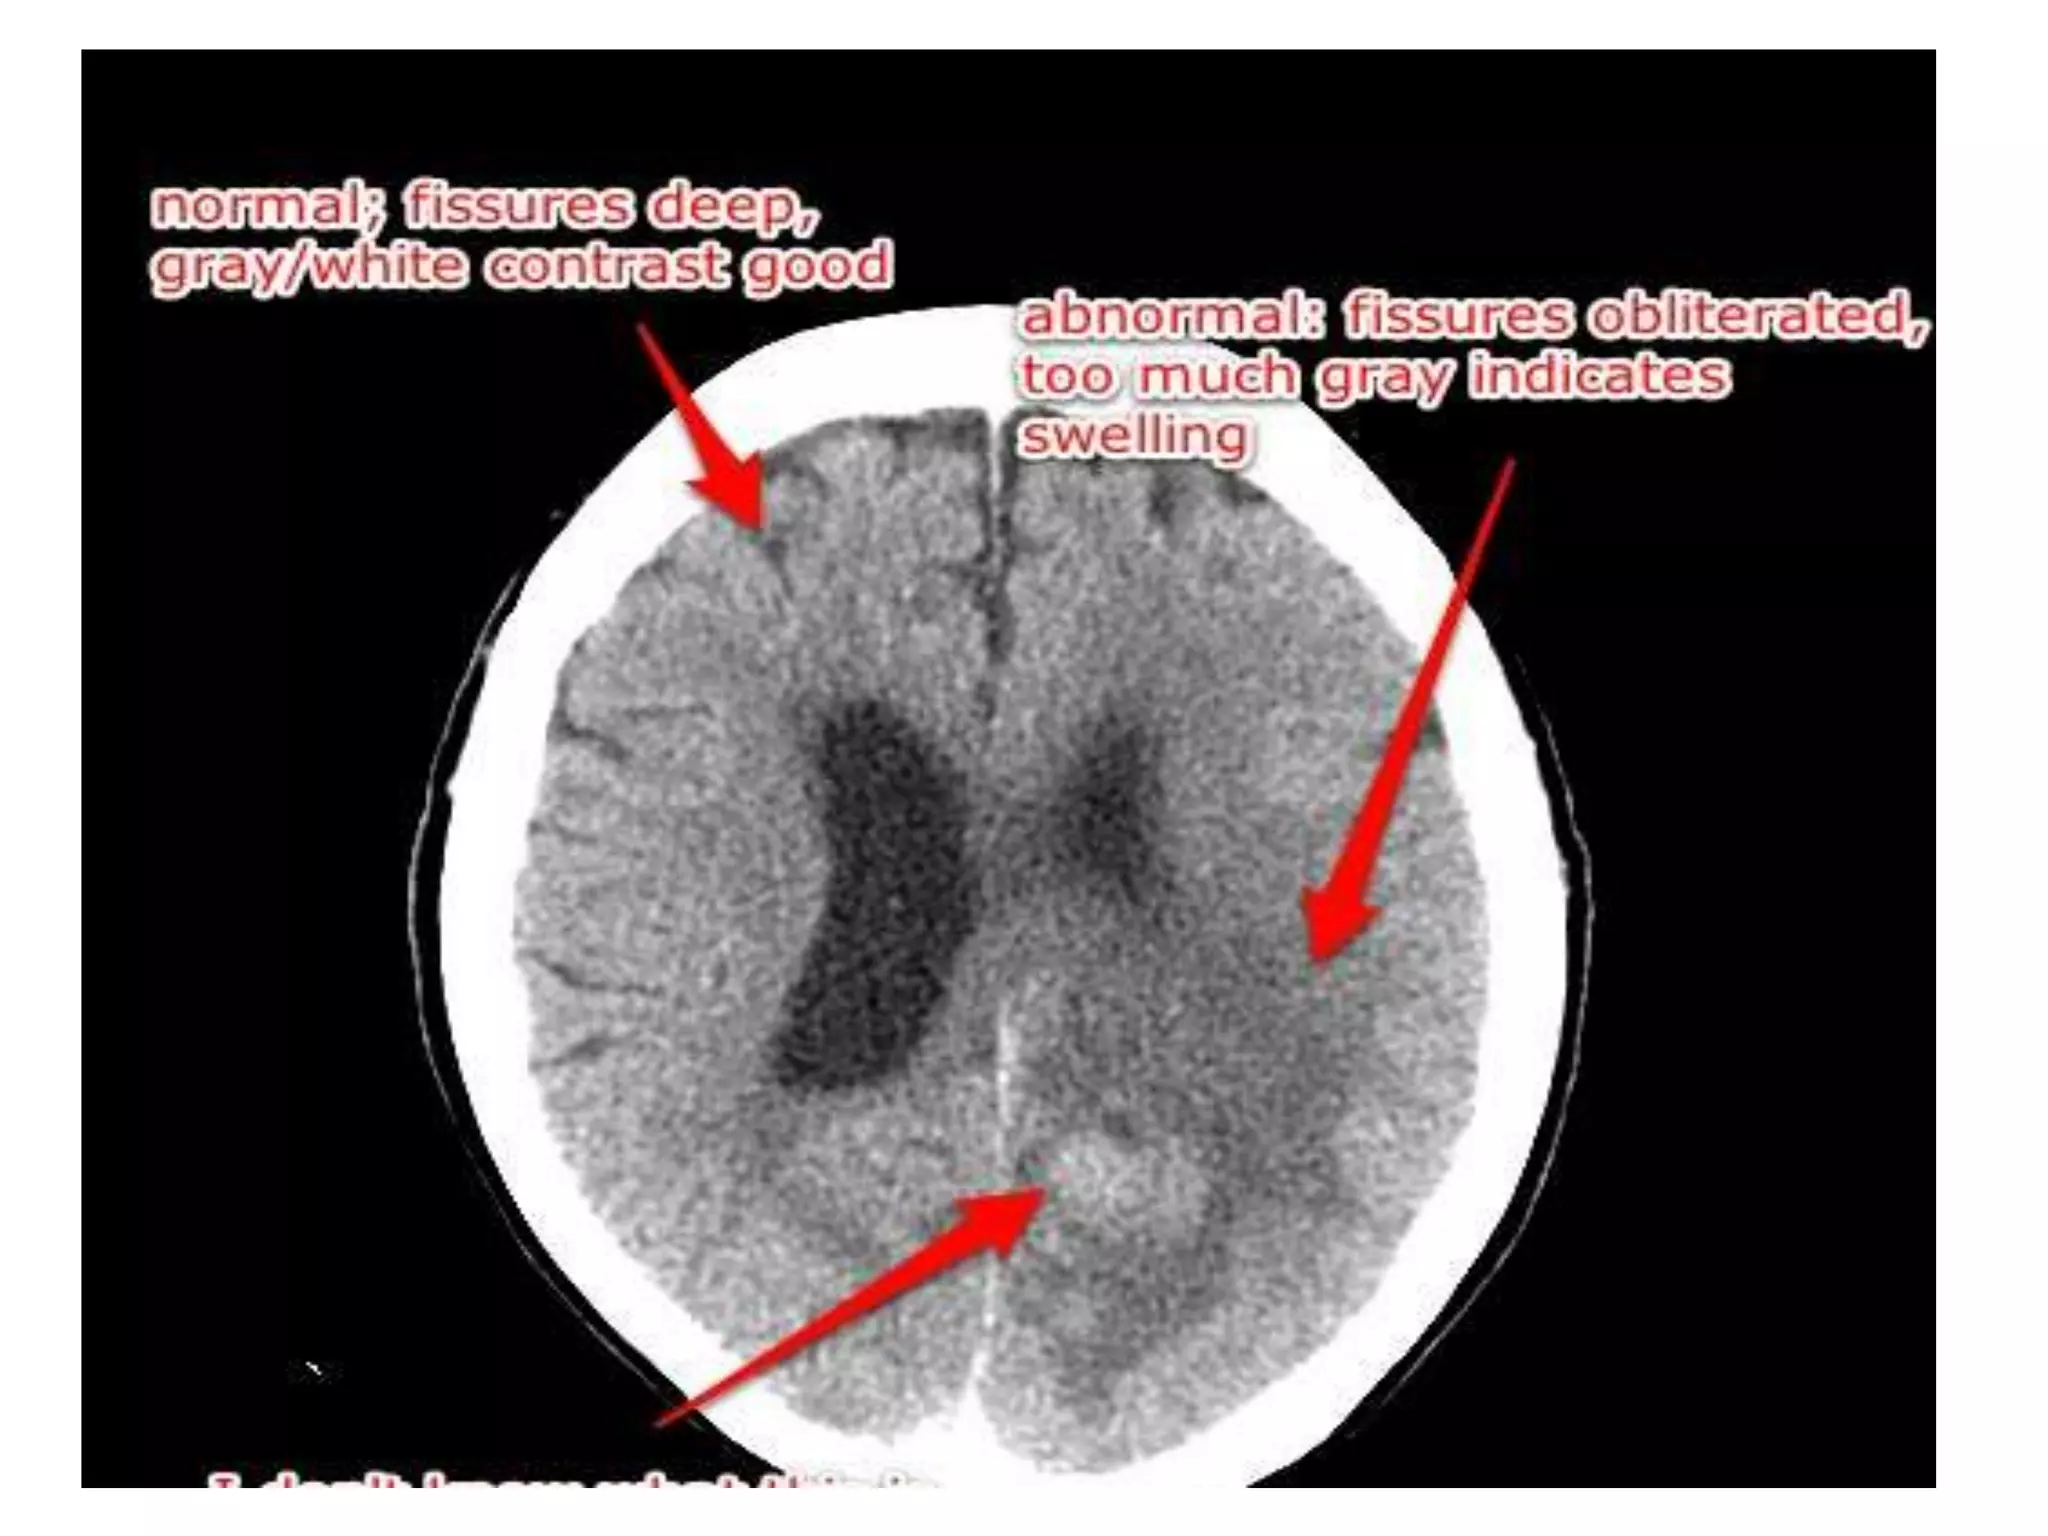

Vasogenic edema:

The amount of edema is greatest in the white matter (increased water and sodium in the

extracellular spaces, decreased potassium); but the same changes may take place in grey

matter but less so.

The astrocytes become swollen.

• This type of edema is seen in response to trauma, tumors,

focal inflammation, and late stages of cerebral ischemia.